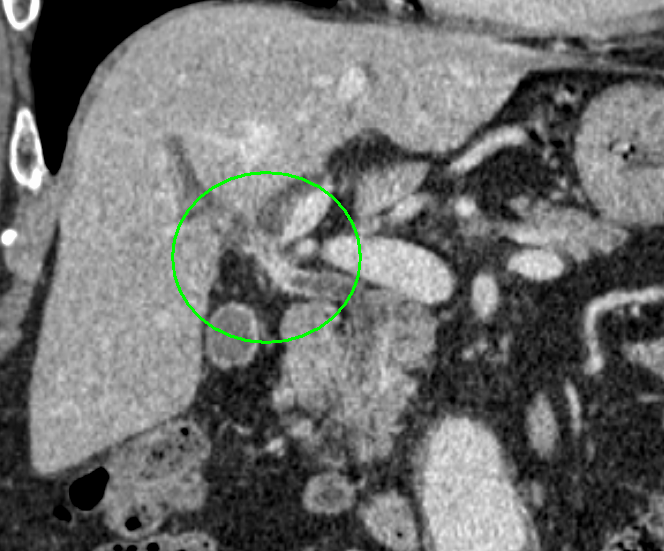

CT画像(肝門部領域胆管がん)